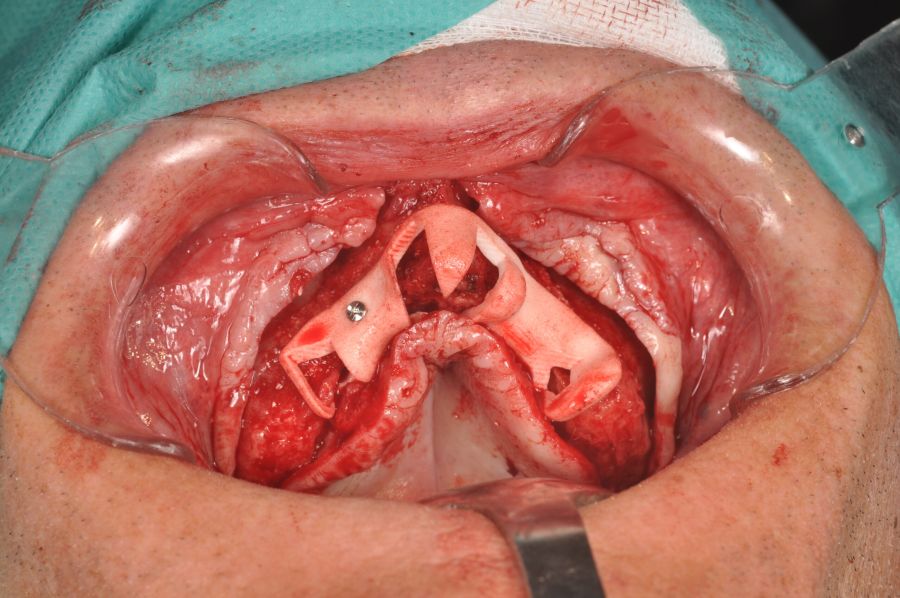

The surgical procedure was performed under general anaesthesia and nasotracheal intubation. A supracrestal incision and detachment of a maxillary flap of total thickness was made (Figures 9 and 10). The boundaries of the dissection were both infraorbital ridges, both laterally malar bodies and the anterior half of the hard palate caudally. In addition, a customized cutting guide was used so that the SI was completely in direct contact with the bone (Figure 11) and the mesh was fixed with the different 1.5 mm osteosynthesis screws in the nasal and zygomatic buttresses (KLS Martin, Freiburg, Germany) (Figure 12). The closure was performed with nonresorbable suture. Finally, the PMMA provisional rehabilitation was screwed for the immediate load, with a torque of 20 N on the implants (Figures 13-15).